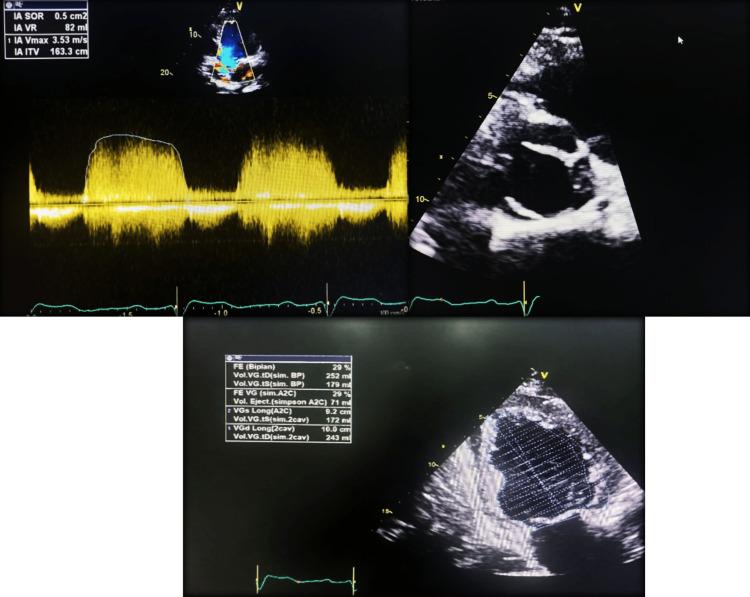

Coronary artery ectasia (CAE) is a rare condition, affecting 3%-8% of patients with atherosclerotic coronary artery disease, and is characterized by the abnormal dilatation of the coronary arteries. While the etiology of coronary artery ectasia encompasses a myriad of acquired and genetic factors, its pathogenesis still remains a subject of investigation. The clinical manifestations are varied, ranging from asymptomatic cases to chest angina and myocardial infarction. Coronary angiography remains the gold standard for diagnosing CAE. We herein report four cases of coronary ectasia: the first involving myocardial infarction, the second associated with bicuspid aortic valve with severe aortic regurgitation, the third detected during coronary angiography for moderate left ventricular dysfunction, and the last one detected during coronary angiography for stable angina. The aims of our study are to highlight the diversity of clinical presentations as well as the challenge of management, given that there are no universal treatments or guidelines.

冠状动脉扩张(CAE)是一种罕见病症,在动脉粥样硬化性冠状动脉疾病患者中占3%-8%,其特征为冠状动脉异常扩张。虽然冠状动脉扩张的病因包括众多后天因素和遗传因素,但其发病机制仍是一个研究课题。临床表现多样,从无症状病例到心绞痛和心肌梗死不等。冠状动脉造影仍然是诊断CAE的金标准。我们在此报告4例冠状动脉扩张病例:第一例伴有心肌梗死,第二例与二叶式主动脉瓣伴严重主动脉瓣反流相关,第三例在冠状动脉造影时因中度左心室功能障碍被检测出,最后一例在冠状动脉造影时因稳定型心绞痛被检测出。鉴于目前尚无通用的治疗方法或指南,我们研究的目的是强调临床表现的多样性以及管理方面的挑战。